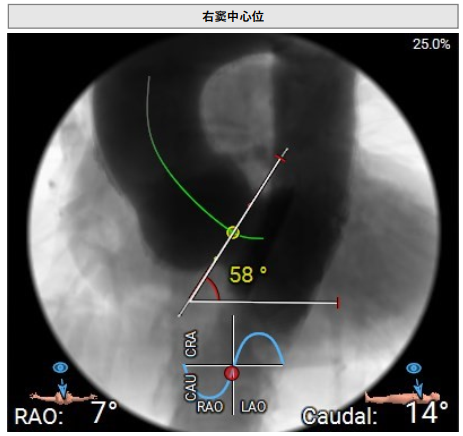

术中回顾及效果

手术过程顺利。术中通过右窦居中造影、定位件入窦造影及释放后功能确认等关键步骤,确保瓣膜锚定准确。器械时间约10分钟。术中超声检查未见瓣周漏,瓣膜位置及功能评估良好,整个过程衔接紧密,无术中并发事件发生。术后即刻超声复查提示人工生物瓣启闭良好,平均跨瓣压差为6mmHg,血流速度正常。患者恢复情况稳定,心功能显著改善。

夹持件顺利入窦